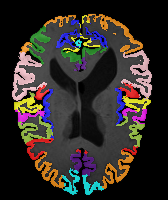

Moving Target Mono-0 Mono-5 DA-1 DA-5 Mono-200 Refer to caption Refer to caption Refer to caption Refer to caption Refer to caption Refer to caption Refer to caption Refer to caption Refer to caption Refer to caption Refer to caption Refer to caption Refer to caption Refer to caption

Image Manual Seg DA-1 Mono-21 DA-21 Mono-65 Refer to caption Refer to caption Refer to caption Refer to caption Refer to caption Refer to caption

Figure 2:  Examples of knee MRI registration (top) and brain MRI segmentation (bottom) results. Top: The first two columns are the moving image/segmentation and the target image/segmentation followed by the warped moving images (with deformation grids)/segmentations by different models. Bottom left to right: original image, manual segmentation, and predictions of various models. Mono-i𝑖i and DA-i𝑖i represent the mono- and DA models with i𝑖i manual segmentations respectively.

Results: All trained networks are evaluated using Dice overlap scores between predictions and the manual segmentations for the segmentation network, or between the warped moving segmentations and the target segmentations for the registration network. Tabs. 1 and 2 show results for the knee and brain MRI experiments respectively in Dice scores (%). Fig. 2 shows examples of knee MRI registrations and brain MRI segmentations.

Qualitative results: DA achieves more anatomically consistent registrations than the mono-networks on the knee (Fig. 2) and Brain MRI samples (see supplementary material).